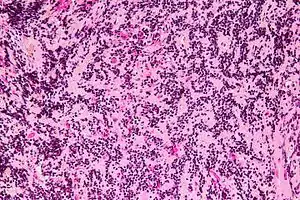

Micrograph of a pineocytoma. HPS stain.

Pineocytomas are diagnosed from tissue, i.e. a brain biopsy.

They consist of:

• cytologically benign cells (with nuclei of uniform size, regular nuclear membranes, and light chromatin) and,

• have the characteristic pineocytomatous/neurocytic rosettes, which is an irregular circular/flower-like arrangement of cells with a large meshwork of fibers (neuropil) at the centre.[1] Pineocytomatous/neurocytic rosettes are superficially similar to Homer Wright rosettes; however, they differ from Homer Wright rosettes as they have (1) more neuropil at centre of the rosette and, (2) the edge of neuropil meshwork irregular/undulating.